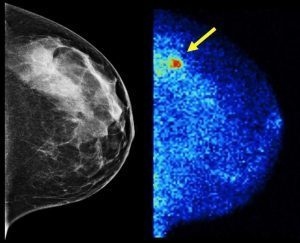

Survival and successful treatment outcomes of breast cancer is so closely linked to tumour size. Early detection is a key component in securing the best possible results for women diagnosed with breast cancer. Breast density is like the wolf in sheep’s clothing. Both tumors and dense breast tissue appear white on a mammogram. A traditional … More Huffington post – breast density “a wolf in sheep’s clothing “